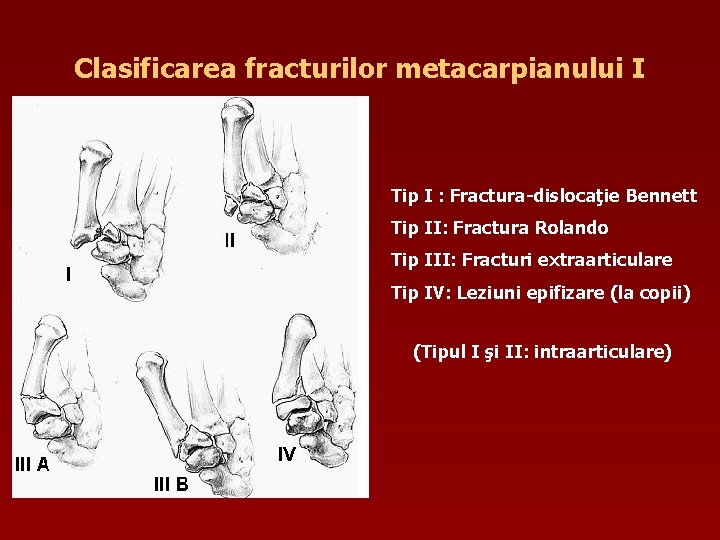

Clasificarea fracturilor metacarpianului I Tip I : Fractura-dislocaţie Bennett Tip II: Fractura Rolando Tip III: Fracturi extraarticulare Tip IV: Leziuni epifizare (la copii) (Tipul I şi II: intraarticulare)